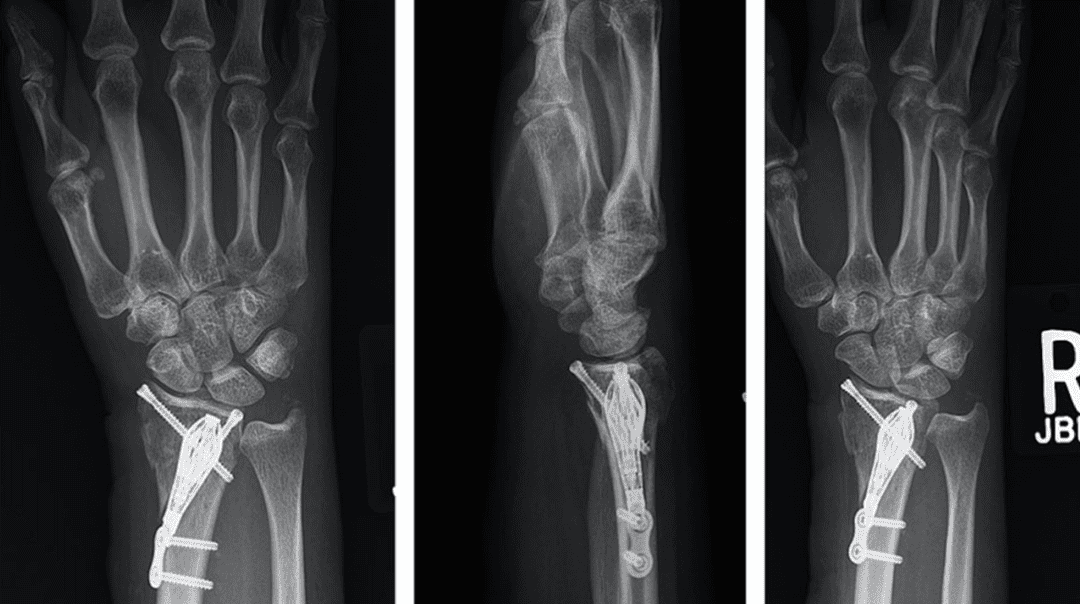

Intrafocal Pin Plate Fixation of Distal Ulna Fractures Associated With

Intrafocal Pin Plate Fixation of Distal Ulna Fractures Associated With Distal Radius Fracture Pinning Technique fixation technique strong evidence suggests no significant difference in radiographic or patient reported. plating techniques allow for more accurate and rigid fixation of fragments with more reliable outcomes. this article describes a modified technique that combines percutaneous pinning and casting. fracture of the distal radius is a common clinical problem. The minimally invasive technique bucks. . Distal Radius Fracture Pinning Technique.